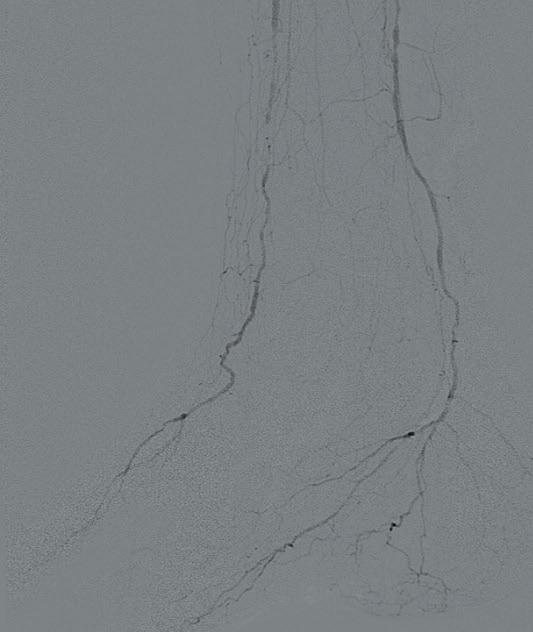

Ultrasound-guided access was obtained in the left common femoral artery and right lower extremity angiography confirmed nonobstructive inflow disease with tandem calcified 70 and 80% P1 as well as P2 extending into P3 disease. The anterior tibial

artery was noted to have a highgrade stenosis proximally with severe diffuse disease throughout its course, with essentially calcified occlusive disease distally with diffuse disease of the dorsalis pedis artery. The TP trunk was occluded proximally with complete occlusions of the TP trunk peroneal and posterior tibial vessels, with reconstitution of the posterior tibial artery above the ankle via geniculate collaterals. There was moderate diffuse disease of the plantar vessels as well (Figure 2a–c).

A 6F Ansel sheath (Cook Medical) was placed in the right CFA, and the anterior tibial occlusion was crossed with an Abbott Command 0.014” wire, followed by treatment of the popliteal lesions with a 6.0x60mm IVL catheter followed by drugcoated balloon (DCB) angioplasty with a Bard 6x150 Lutonix balloon, with reduction to a <30% residual. The right anterior tibial artery was treated with a 3.5x60mm

IVL catheter along a ~20cm segment of the lesion, followed by percutaneous transluminal angioplasty (PTA) with a 3x3.5x210mm Nanocross balloon (Medtronic), with an excellent result without recoil, despite the heavy calcific burden of disease. Antegrade traversal of the TP trunk and posterior tibial arteries was unsuccessful despite an escalating wire strategy, so

the posterior tibial artery was accessed in a retrograde manner with ultrasound guidance. The 0.014” Abbott Command wire was eventually delivered to the common femoral artery using a Quick-Cross 0.014” support catheter (Spectranetics) and exteriorised using a 7mm goose neck snare (Microvena). IVL of the TP trunk and proximal posterior (approximately 20cm of treatment length) tibial artery was performed with a 3.5x40 S4 IVL catheter in less than five minutes. This was followed by PTA distally with a tapered 3x3.5x210mm Nanocross balloon. A 4x38mm Medtronic Resolute Onyx DES was placed to treat a residual dissection in the TP trunk with final angiography demonstrating three-vessel runoff to the foot (Figure 3a–c). Remarkably, the anterior tibial IVL/PTA result showed no appreciable recoil, despite the fact that it took over 90 minutes to complete the TP trunk and posterior tibial reconstruction. He was discharged later that day. He later underwent second toe amputation and successfully healed his wounds.

This case illustrates the utility of IVL not only for superior acute luminal gain in calcified vessels, but also for the lack of recoil that is commonly seen with PTA. Despite the length and complexity of the multiple lesions, treatment required less than five minuted per catheter.

Figure 3a Figure 3b Figure 3c